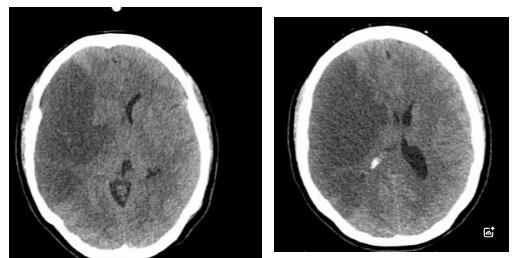

2025年10月11日,42岁的女性患者因突发左侧肢体无力、呕吐、意识障碍等症状被紧急送医。医院立即开启绿色通道,迅速完成头颅MRI检查,并在黄金时间窗内实施了阿替普酶静脉溶栓治疗。次日,患者病情急剧恶化,出现严重脑水肿并形成脑疝。虽曾考虑转往西宁进一步救治,但因路途遥远、转运风险巨大,加之患者家属对医院充满信任,最终决定留在囊谦县人民医院继续治疗。

在医疗条件相对有限的高原县城,救治团队克服困难,对患者进行了不间断的严密监测,连续追踪头颅CT影像变化。经过数个日夜的坚守和精心治疗,患者的病情终于出现了转机。至10月22日复查显示,致命的脑疝得到缓解,脑水肿范围显著缩小,患者成功度过了最危险的阶段,病情逐步稳定下来。